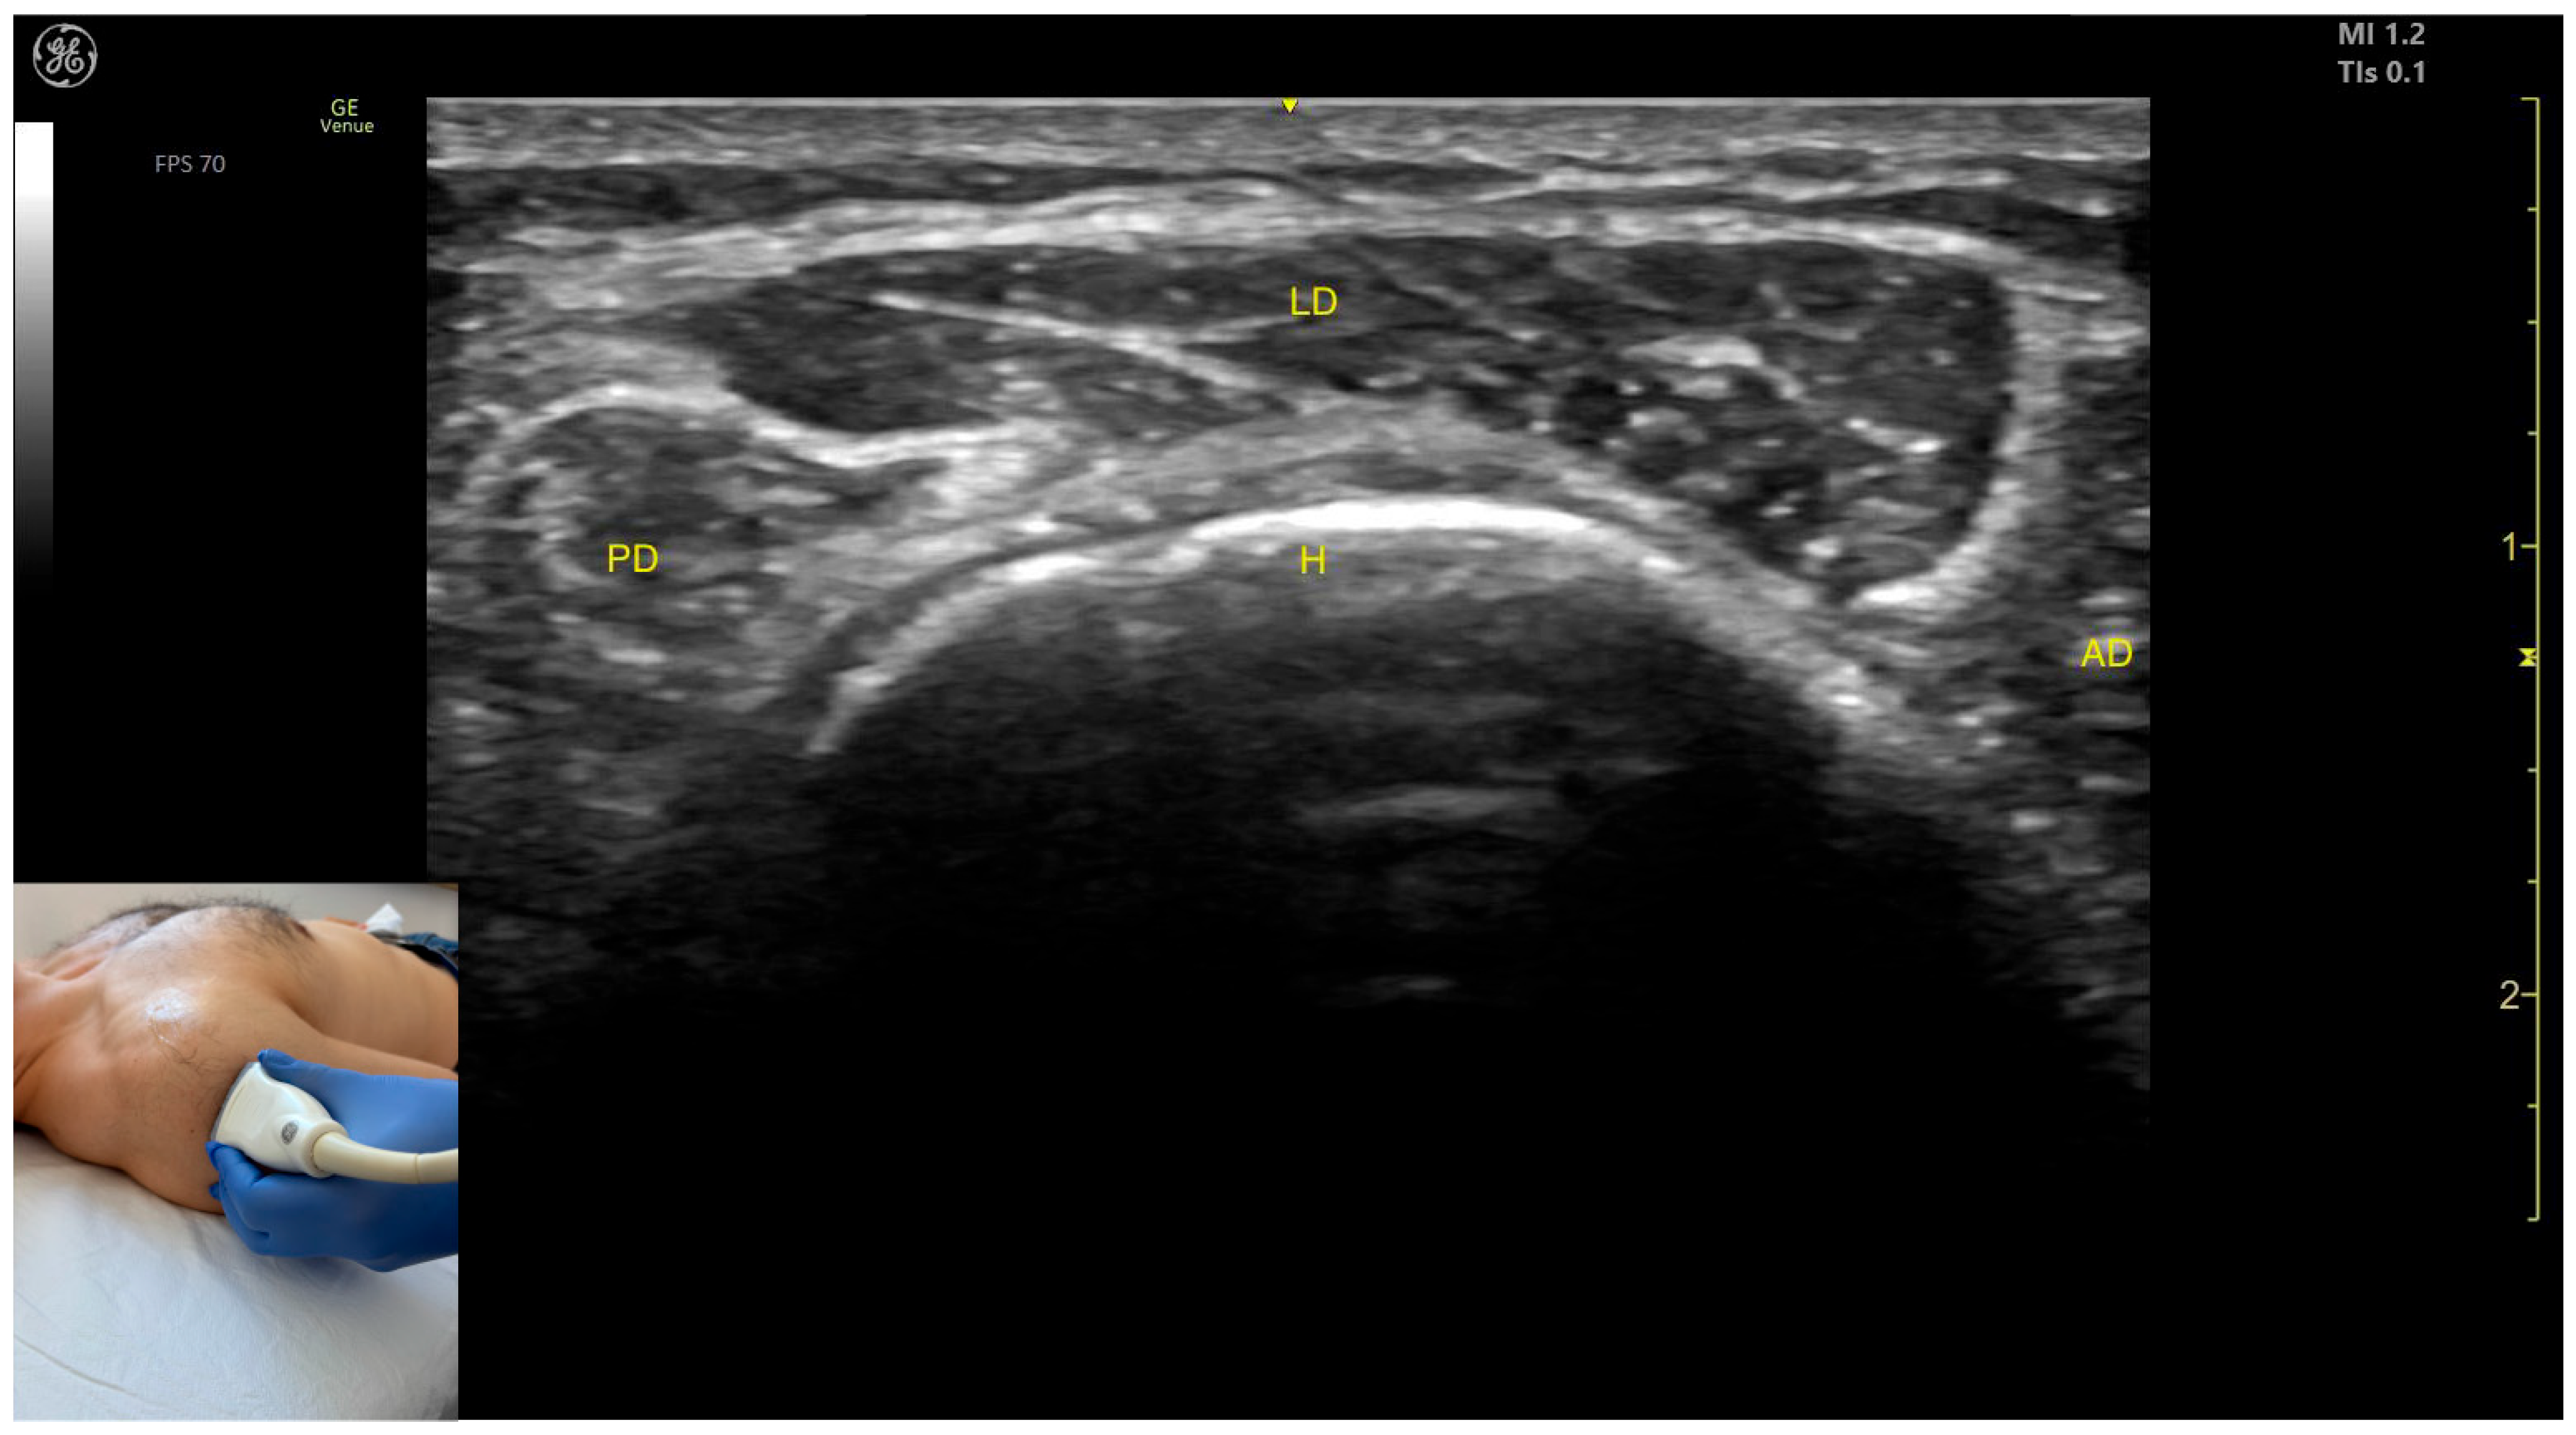

2.6.3. The Acromial Part of the Deltoid Muscle

Ultrasound Identification

Key Ultrasound Landmarks

- Muscle position: It represents a superficial muscle mass on the anterolateral surface of the proximal arm. The AD is observed anterior to the LD, while the posterior deltoid is observed posterior to it.

- External fascia: The LD has a pronounced fascia that separates it from the anterior and posterior deltoid parts, as well as from the subcutaneous plane during BoNT-A injections.

2.6.4. The Spinal Part of the Deltoid Muscle

- Muscle position: It represents a superficial muscle mass on the posterior surface of the proximal arm. Deep to the PD, the infraspinatus muscle and the glenoid labrum are observed.

- External fascia: The PD has a pronounced fascia that separates it from the infraspinatus muscle and the subcutaneous plane during BoNT-A injections.

- Dynamic evaluation: During dynamic evaluation, the origin of the PD at the spine of the scapula is seen when scanning proximally [41]. Contraction of the PD is visible during dynamic assessment when performing maneuvers involving adduction, extension, and lateral rotation of the arm at the shoulder joint [12,39].

2.6.5. Clinical Implications and Injection Strategy

- For the AD, the transducer is placed transversely on the anterior surface of the proximal arm, approximately 2–3 cm distal to the clavicle.

- For the LD, the transducer is positioned transversely on the anterolateral portion of the proximal arm, approximately 2–3 cm distal to the acromion.

- For the PD, the transducer is placed transversely on the posterior surface of the proximal arm, approximately 2 cm distal to the spine of the scapula.